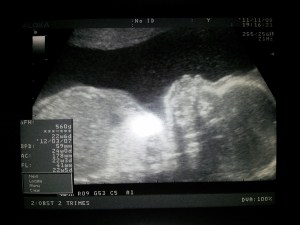

22 semanas inside

El gine nos sacó una eco genial en la que se le ve de perfil y es que se le ven unos mofletacos para comérselos… Aaains, ¡¡Qué ganitas tenemos de conocer al «pequeño» Óscar!! ^_^